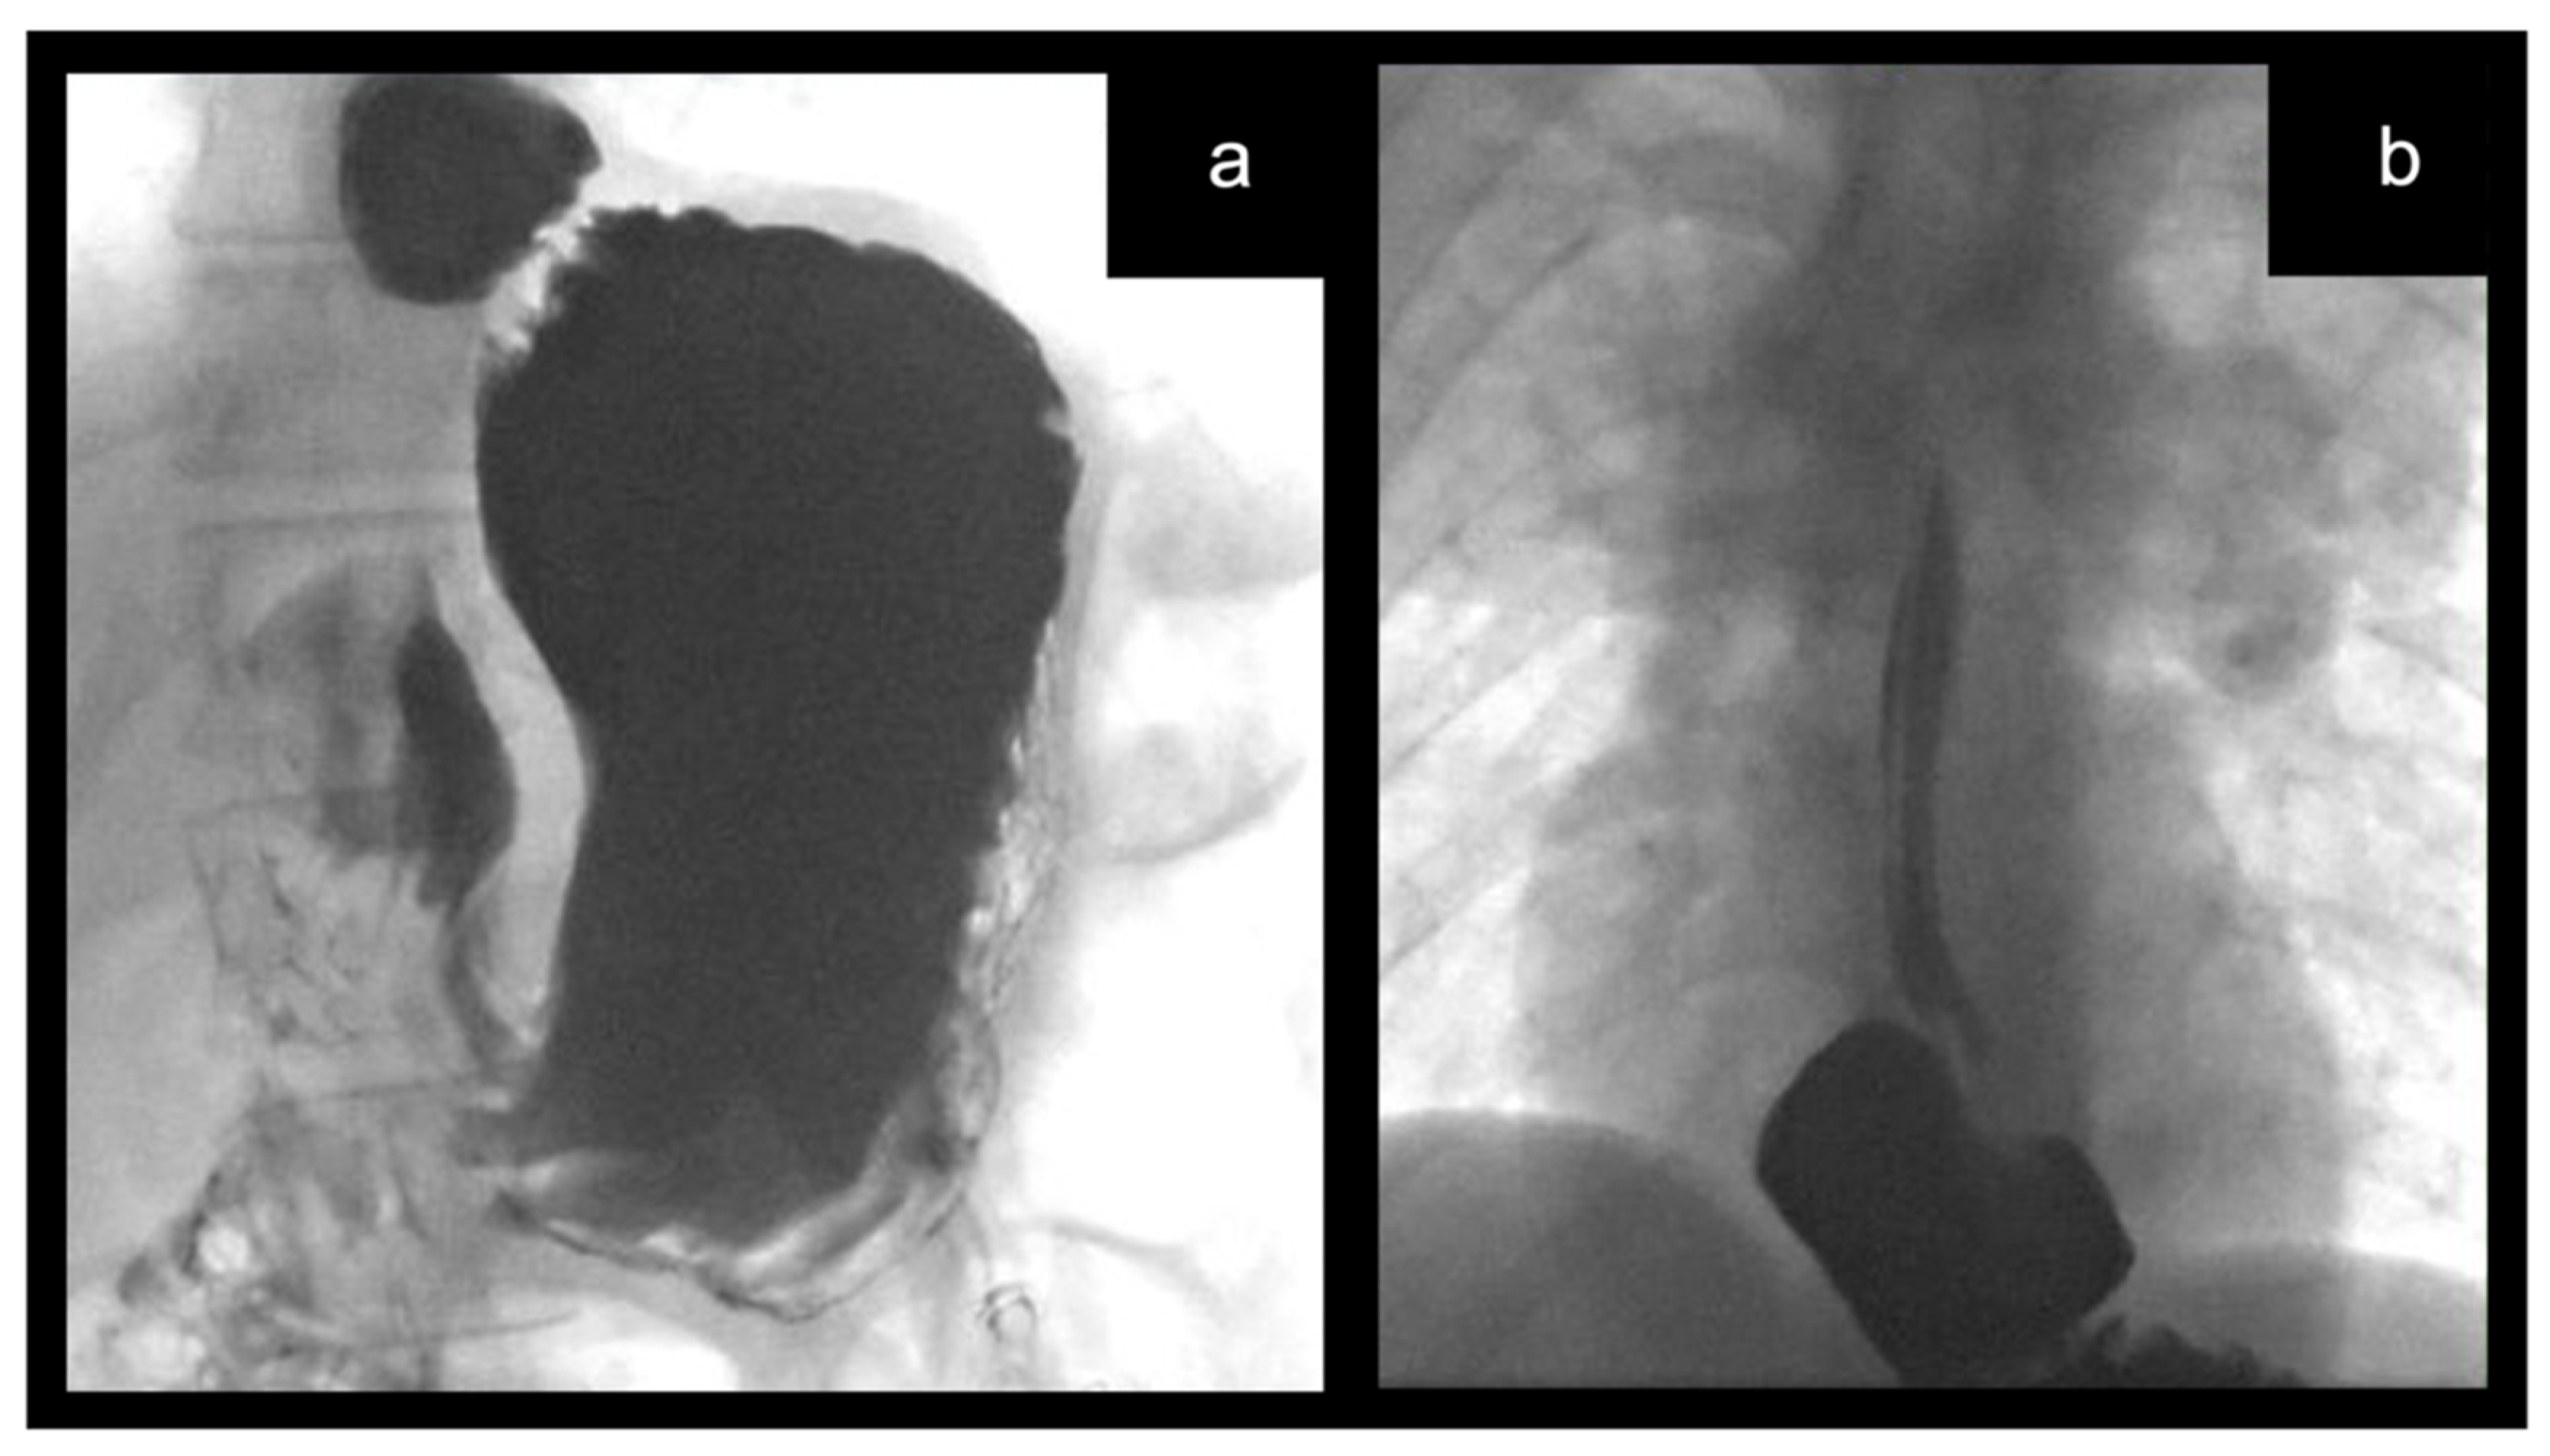

2. Surgical Technique